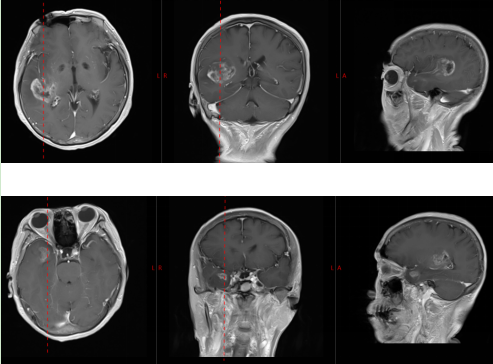

據(jù)了解,71 歲的吳奶奶(化名)近半年來反復(fù)出現(xiàn)頭痛癥狀,近期伴隨頭暈加重,在當(dāng)?shù)蒯t(yī)院行頭部磁共振檢查后,發(fā)現(xiàn)顱內(nèi)存在多個占位性病變。

磁共振顯示顱內(nèi)多發(fā)占位